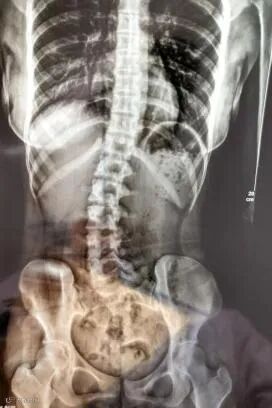

之前,就有新闻报道过一位18岁少女因为睡姿不对,而导致脊柱弯曲。

正常脊柱